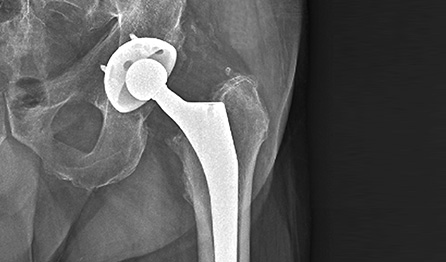

수술치료 [고관절 전치환술]

대퇴 골두와 골반 비구를 일정 부분 잘라낸 후

인공관절을 삽입하여 관절로서의 역할을

할 수 있게 만드는 치료

입니다.